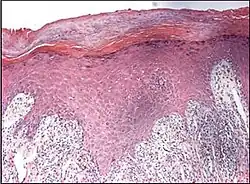

Interface dermatitis with lichenoid inflammation

| Generally/Not otherwise specified | Typical findings:[2]

||

| Lichen planus | Irregular epidermal hyperplasia with a jagged “sawtooth” appearance, compact hyperkeratosis or orthokeratosis, foci of wedge-shaped hypergranulosis, basilar vacuolar degeneration, slight spongiosis in the spinous layer, and squamatization. The dermal papillae between the elongated rete ridges are frequently dome shaped. Necrotic keratinocytes can be observed in the basal layer of the epidermis and at the dermal-epidermal junction. Eosinophilic remnants of anucleate apoptotic basal cells may also be found in the dermis and are referred to as “colloid or civatte bodies”. Whickham striae are usually seen in the areas of hypergranulosis. Vacuolar degeneration at the basal layer may be noted leading to focal subepidermal clefts (Max Joseph spaces). Squamatization occurs as a result of maturation and flattening of cells in the basal layer. It happens in areas of marked hypergranulosis with prominence of the sawtooth pattern of rete ridges. Wedge-shaped hypergranulosis can occur in the eccrine ducts (acrosyringia) or hair follicles (acrotrichia). In the hypertrophic subtype, the associated hyperkeratosis, parakeratosis, hypergranulosis, papillomatosis, acanthosis, and hyperplasia markedly increased with thicker collagen bundles forming in the dermis. Moreover, the rete ridges are more elongated and rounded as opposed to the typical sawtooth pattern. In atrophic LP, loss of the rete ridges and dermal fibrosis is prominent. In vesiculobullous LP, the disease progression is quicker. Hence, some of the distinctive features such as hyperkeratosis, hypergranulosis, or dense lymphocytic dermal-epidermal infiltrate may not be present. LP lesion may resolve with residual hyperpigmentation caused by a persistent increase in the number of melanophages in the papillary dermis.[9] | ![]() |

Interface dermatitis with lichenoid inflammation, not otherwise specified, can be caused by lichen planus-like keratosis, lichenoid actinic keratosis, lichenoid lupus erythematosus, lichenoid GVHD (chronic GVHD), pigmented purpuric dermatosis, pityriasis rosea, and pityriasis lichenoides chronica.[2] Unusual conditions that can be associated with a lichenoid inflammatory cell infiltrate are HIV dermatitis, syphilis, mycosis fungoides, urticaria pigmentosa, and post-inflammatory hyperpigmentation.[2] In cases of post-inflammatory hyperpigmentation, it is important to exclude potentially harmful mimics such as a regressed melanocytic lesion or lichenoid pigmented actinic keratosis.[2]